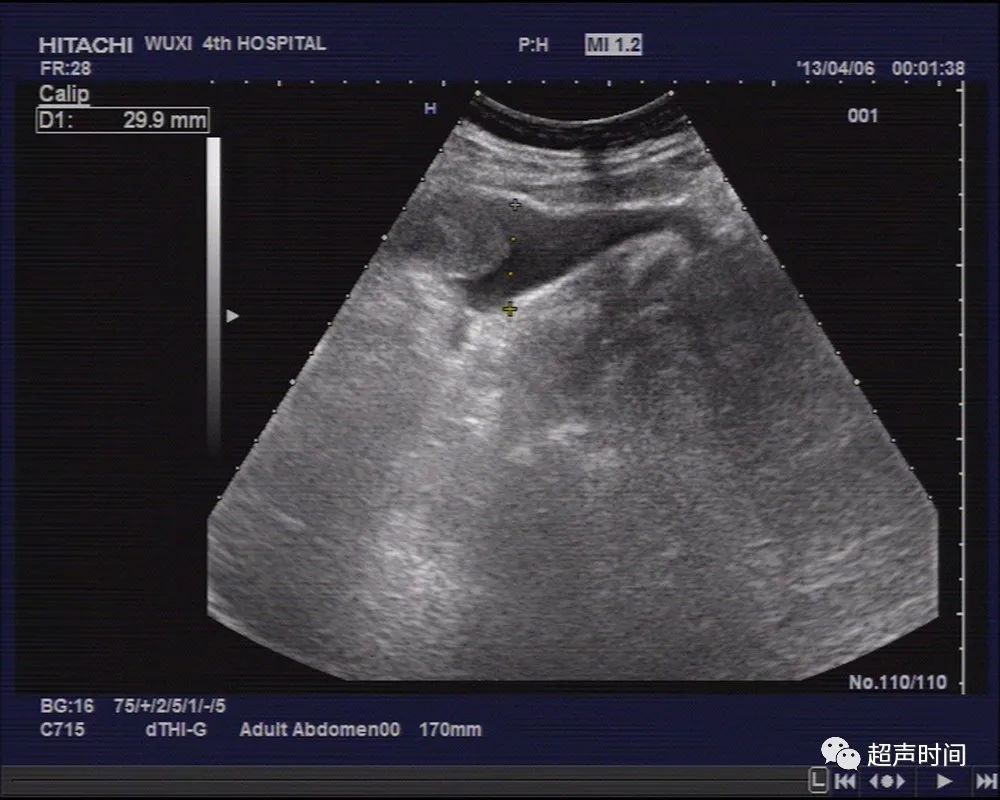

另于盆、腹腔探及液性暗区,最深约 30mm ,透声欠佳(图 3 ~ 5 )。

图 3 盆腔探及液性暗区,最深约 30mm ,透声欠佳